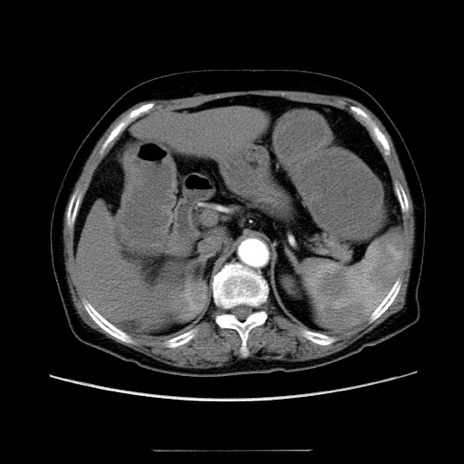

冠状断像

【症例】70歳代女性

【主訴】お腹が張る

【現病歴】1週間くらい前から腹部膨満の自覚あり。昨日夜から増悪したため、本日救急外来受診。

【身体所見】意識清明、BT 36.5℃、BP 165/106mmHg、HR 80bpm、SpO2 98%、腹部:膨満、軟、自発痛・圧痛なし、触診にて不快感あり、腸蠕動音:減弱

【データ】WBC 12600、CRP 1.04